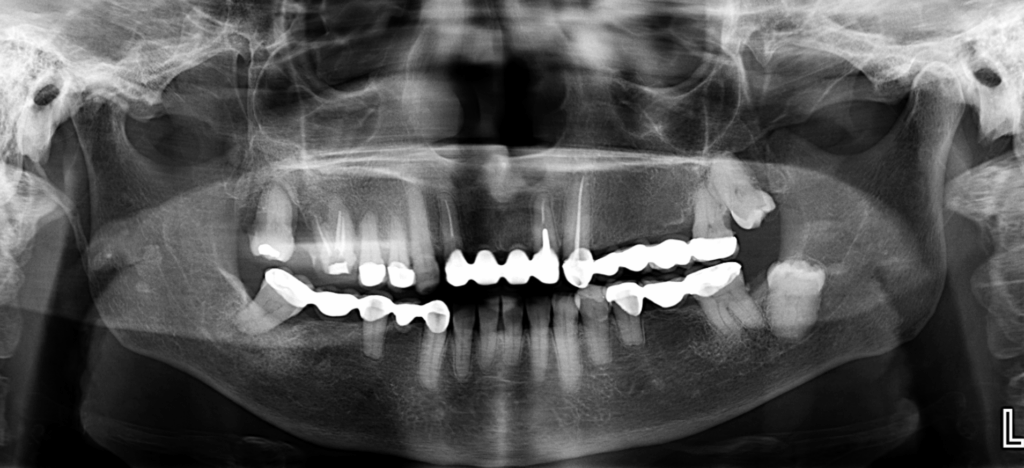

Paciente femenina de 72 años acude a IDM para realizarse una tomografía para evaluación general, al observar la radiografía panorámica se puede observar una mineralización del proceso estilohioideo del lado derecho, aplanamiento del contorno condilar del lado derecho, presencia de placa mineralizada y rebasorción alveolar con presencia de contornos irregulares, múltiples coronas protésicas y piezas dentarias 16, 12, 21, 23 con obturación de conductos, asi como la retención de la pieza 38 y su Hipercementosis, etc.

Sin embargo a nivel de la rama mandibular del lado derecho se observan múltiples imágenes radiopacas de forma irregular que a su vez ocasionan imágenes fantasmas en el lado contra lateral.

Radiografia Panorámica